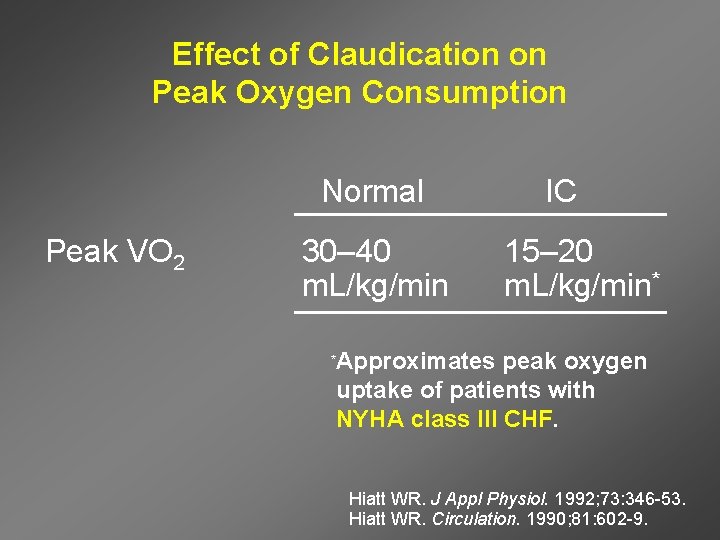

Effect of Claudication on Peak Oxygen Consumption Normal Peak VO 2 30– 40 m. L/kg/min * IC 15– 20 m. L/kg/min* Approximates peak oxygen uptake of patients with NYHA class III CHF. Hiatt WR. J Appl Physiol. 1992; 73: 346 -53. Hiatt WR. Circulation. 1990; 81: 602 -9.